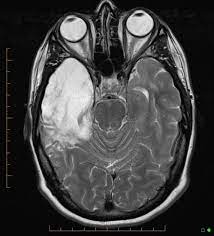

A 40‑year‑old male patient with herpes simplex virus encephalitis presented with altered sensorium. The differential diagnoses include limbic encephalitis (paraneoplastic), gliomatosis cerebri, and status epilepticus. Herpes simplex (hsv) encephalitis is the most common cause of fatal sporadic fulminant necrotizing viral encephalitis and has characteristic imaging findings. Severe edema, petechial hemorrhage, and massive hemorrhagic tissue necrosis can be seen on gross specimens. Two subtypes are recognized which differ in demographics, virus, and pattern of involvement.

Watershed distribution ischemia in areas remote from the primary herpetic lesions may be seen. Herpes simplex encephalitis typically manifests in older adults (about 50% of cases) with headache, fever, altered sensorium, and even seizure. Hippocampus, temporal lobe, and the ponsfigure 4a.7. Herpes simplex virus (hsv) is the most common cause of acute fatal sporadic encephalitis, with a particular predilection for the limbic system. Unfortunately, the imaging findings are often nonspecific with overlapping appearances. This lesion was seen in all patients as the disease progressed. Severe edema, petechial hemorrhage, and massive hemorrhagic tissue necrosis can be seen on gross specimens. He was managed with intravenous acyclovir 30mg/kg and supportive therapy. that appeared in a recent issue of clinical infectious diseases. However, mimics of hse, including other infections and increasingly recognized autoimmune causes, have been described in cases of tl encephalitis. But changes are not specific for hsv (e.g. The characteristic feature of hse is hemorrhagic necrosis of the temporal lobe. The basal ganglia are usually spared.

A feasibility study of quantifying longitudinal brain changes in herpes simplex virus (hsv) encephalitis using magnetic resonance imaging (mri) and stereology. In the present study, flair bth was most frequently seen in patients with hsv encephalitis. Mri is the diagnostic modality of choice abnormal in 90%; Herpes simplex virus (hsv) encephalitis hsv encephalitis (hsve) is the most common cause of infectious encephalitis (1); The basal ganglia are usually spared. Encephalitis, magnetic resonance imaging, meningoencephalitis, viral. that appeared in a recent issue of clinical infectious diseases. Although far less common, essentially any part of the central nervous system can be involved 9. 1 mri t2 weighted image, showing bilateral temporal lobe hyperintensities. However, mimics of hse, including other infections and increasingly recognized autoimmune causes, have been described in cases of tl encephalitis. Two subtypes are recognized which differ in demographics, virus, and pattern of involvement. Because early diagnosis is possible in more cases of herpes simplex encephalitis (hse) as a result of the high sensitivity of mri, now widely available, a larger number of patients are receiving appropriate treatment with iv acyclovir. Limbic encephalitis, mca ischaemia, tumours, effects of seizures) hyperintense t2 signal in the medial temporal lobes, inferior frontal lobes and insula basal ganglia are usually spared

that appeared in a recent issue of clinical infectious diseases hsv encephalitis mri. (a) on presentation there may be unilateral or bilateral asymmetric involvement of limbic system structures, including the temporal lobes, insulae, and cingulate gyri.